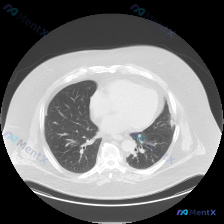

看到一个左肺下叶孤立性结节的病例资料,整理了一下分析思路。 基本信息与影像表现: 患者胸部CT肺窗横断面图像显示,在左肺下叶(背段/基底段)可见一类圆形、边界尚清的结节影,直径约1-1.5cm,密度均匀,未见明显钙化或空洞。双肺肺野透亮度基本均匀,未见弥漫性密度增高影或过度通气表现,双侧主支气管及叶...